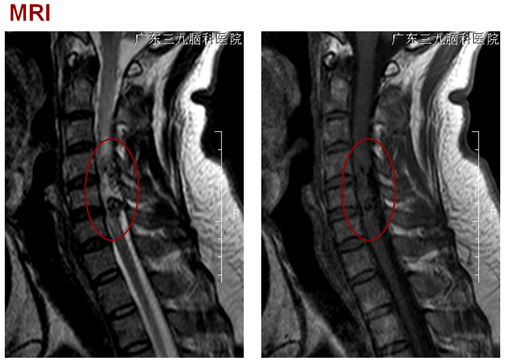

颈4-6水平脊髓内(偏右后部)病变及延髓至颈6水平脊髓周缘线状强化影,考虑为动静脉畸形,并颈髓水肿。